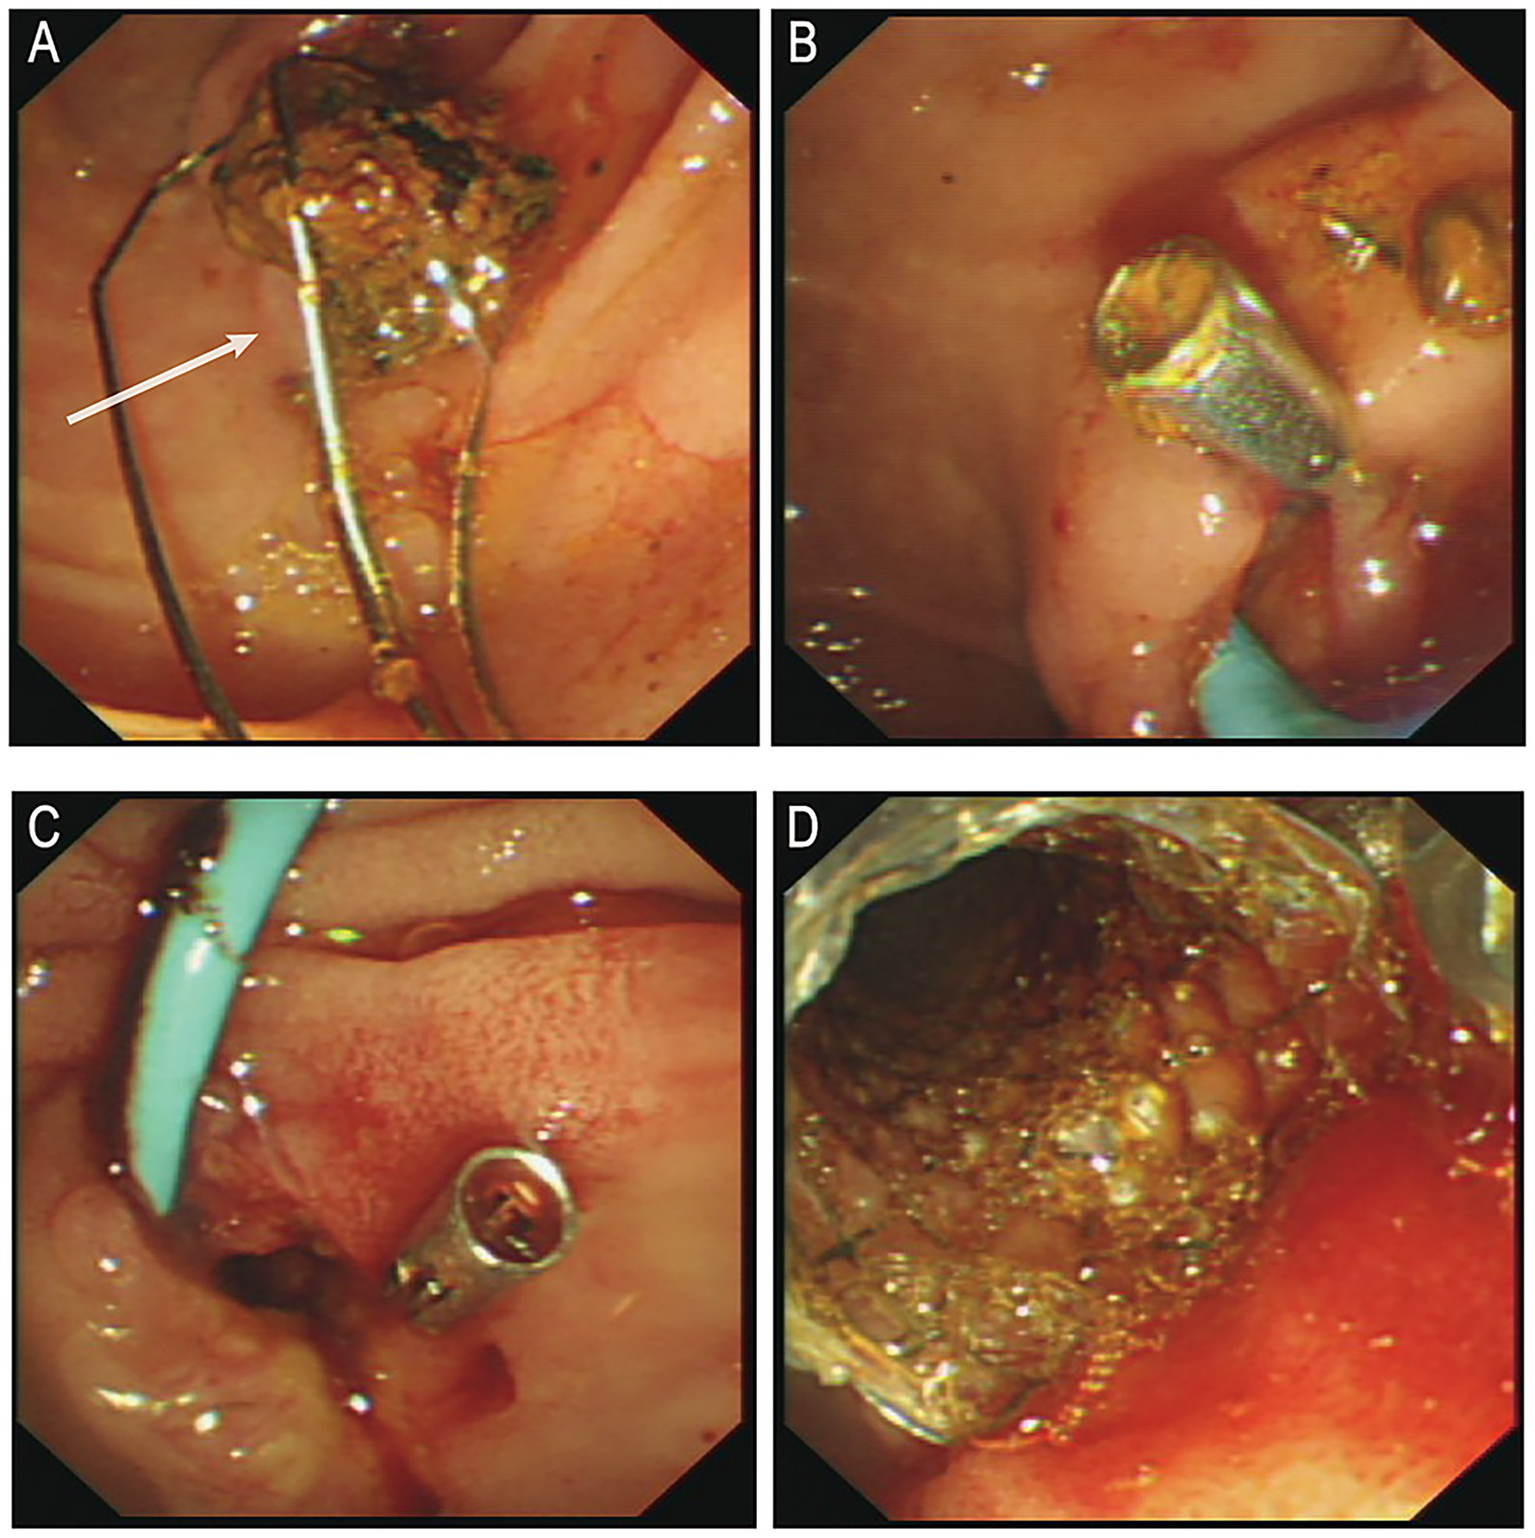

Following anti-infective and supportive treatment, ERCP was performed on June 25. During the procedure, endoscopic sphincterotomy was carried out, and a cylindrical balloon with a diameter of 1.1 cm was used to dilate both the distal common bile duct and the duodenal papilla. A stone retrieval basket (Four-line spiral type) was then employed to successfully extract a common bile duct stone measuring approximately 1.5 × 1.6 cm (Figure 2A). After the procedure, one titanium clip was applied at the sphincterotomy site to prevent post-EST bleeding, and a nasobiliary drainage tube was placed for bile drainage (Figure 2B). Six hours after the first ERCP, the patient’s serum amylase and lipase levels were transiently elevated (240 U/L [normal range: 35–135 U/L] and 455 U/L [normal range: 1–60 U/L], respectively), but both values returned to normal within 10 h (109 U/L and 62 U/L, respectively).

Figure 2

(A) Post-stone extraction. (B) Post-operative placement of titanium clamps and nasal bile duct drainage tube. (C) Active bleeding observed in the bile duct. (D) Post-hemostasis following metal stent placement. ERCP, endoscopic retrograde cholangiopancreatography. White arrows indicate the extracted stone.